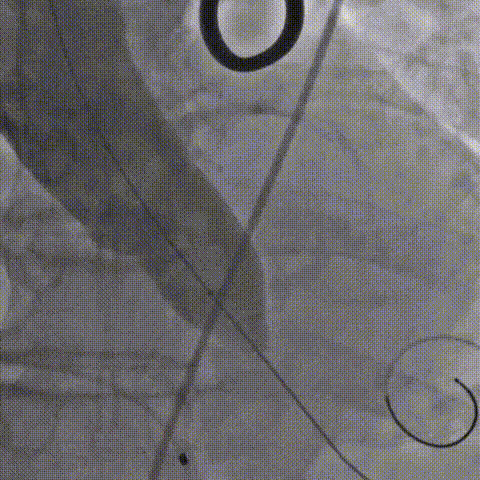

3.25mm球囊预扩,轻微腰征,双侧冠脉显影良好,决定选择29号瓣膜。

球囊预扩

4.瓣膜释放到工作位后,造影显示位置良好,锚定充分,继续旋转手柄,瓣膜逐一脱钩,顺利释放。

瓣膜定位

5.释放后瓣膜展开不充分,决定采用25mm球囊后扩,造影提示瓣膜充分展开,位置良好,瓣周微量反流

手术造影